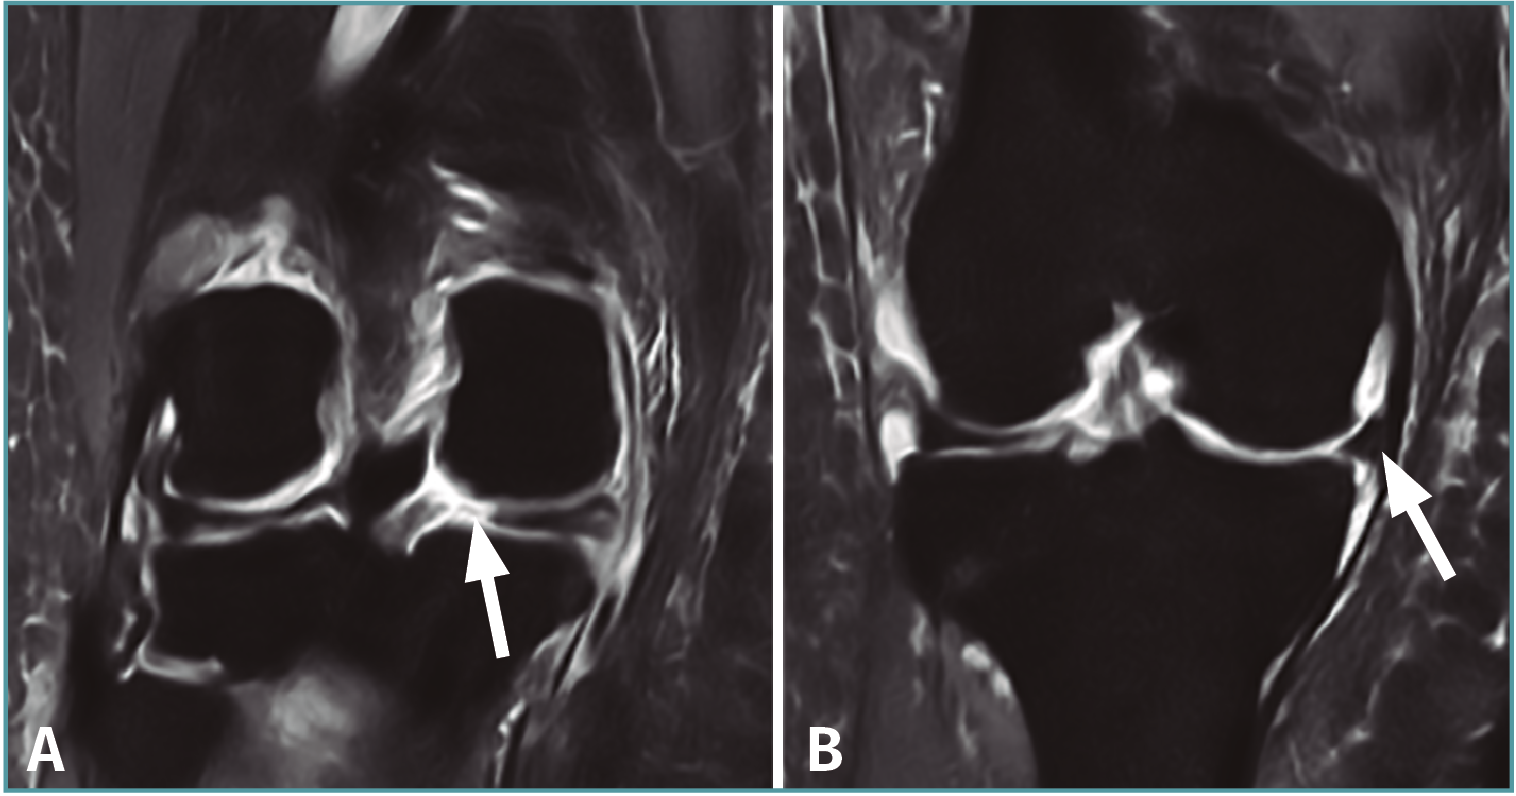

En el plano coronal permite una mejor definición de la raíz, la cual debería discurrir intacta por encima del respectivo platillo tibial en al menos una imagen(2,16).

Además, este plano es óptimo para la valoración de la extrusión meniscal o desplazamiento del menisco sobre el borde del platillo tibial, la cual es significativa cuando es superior a 3 mm del menisco sobre el borde tibial(59)(Figura 7). Dicha extrusión, si bien puede aparecer en las roturas horizontales, es de menor entidad en comparación con los desgarros radiales, en especial con las roturas completas, siendo más frecuente en la afectación del menisco medial(59). Esto último es debido a que el menisco lateral se encuentra estabilizado por los LMF, por lo que para que aparezca una extrusión del mismo es necesaria una rotura asociada de dichos ligamentos.

Figura 7. Imágenes coronales de resonancia magnética de una rodilla con rotura de la raíz posterior del menisco medial. A: corte a nivel del cuerno posterior, donde se aprecia la rotura (flecha); B: corte a nivel del cuerpo del menisco, donde puede apreciarse la extrusión del mismo (flecha).